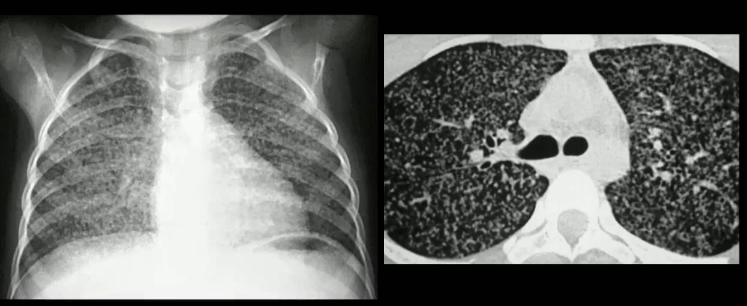

TBC Miliar

Rx Tx: pequeños nódulos del tamaño de un grano de mijo diseminados en ambas playas pulmonares.

Dx: se confirma con punción pulmonar y biopsia.